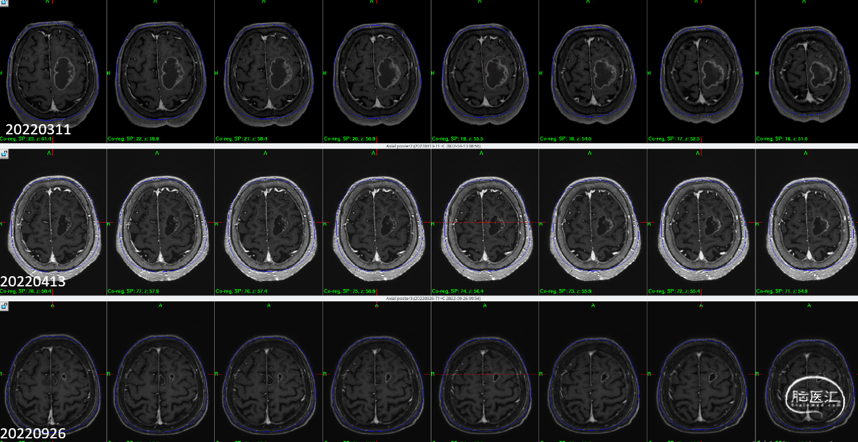

6个月随访

临床随访:神志清楚,言语流利,认知功能正常,无癫痫发作,右侧肢体肌力5级,可独立行走。

影像随访:

1)左额病灶:囊性病变逐渐缩小

6个月随访时,薄扫增强磁共振(1mm/层)提示肿瘤明显缩小,无放射相关不良反应,没有新发病灶;患者目前仍在规律的随访当中,期待我们的长期随访结果。